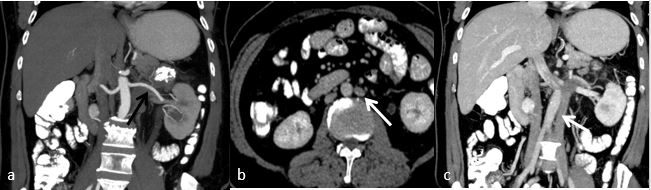

A 61-year old male referred to the urology clinic with a palpable mass in the lower left abdomen and hematuria. A contrast-enhanced CT scan revealed a heterogeneous peripherally enhanced tumor with a central hypovascular area (Figures 1 and 2); clinicoradiologically RCC was suspected and left radical nephrectomy was performed. Grossly, a well-circumscribed solid, beige tumor measuring 7 x 6 x 7cm, located in the upper pole of the left kidney with variegated areas where extensive bony hard calcification were noted (Figure 3). Sections showed a biphasic tumor, having epithelial tumor cells arranged in lobules, sheets and vague nodular pattern separated by fibrovascular septa, which were histomorphologically in favor of CRCC. Large proportion of sarcomatoid areas, dystrophic calcification and lacy malignant osteoid intermingled with malignant spindle cells (osteosarcoma component) were also noted (Figure 4). Large areas of hemorrhage and coagulative necrosis were present. Epithelial tumor cells were immunoreactive for CK7 and E-cadherin and immunonegative for CD10 and Vimentin (Figure 5). The sarcomatoid areas were immunopositive for Vimentin. There were perinephral tumor deposits, lymph node metastasis and perineural invasion. The final diagnosis was given as CRCC with sarcomatous differentiation containing osteosarcoma component.

Fig. 2. CECT abdomen (a) showing single left renal artery (black arrow) and (b, c) images showing duplication of IVC on both side of aorta. Left renal vein draining into left side IVC (white arrow).